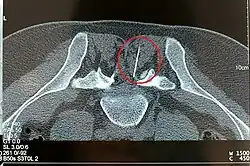

Dabei wird das zu behandelnde Segment der Wirbelsäule mittels Röntgendurchleuchtung oder Computertomographie eingestellt und abgebildet. Anhand dessen plant und steuert der Arzt die Stichrichtung und die Stichtiefe für die Platzierung der PRT-Nadel. Nach Hautdesinfektion und gegebenenfalls lokaler Betäubung des Stichkanals wird die PRT-Nadel platziert. Nach Lagekontrolle mit erneuter Bildkontrolle und – fakultativ – der Gabe von etwas Kontrastmittel werden die Medikamente appliziert. Unter Nutzung von anatomischen Landmarken ist oft auch eine Durchführung ohne zusätzliche bildgebende Verfahren möglich.[1]